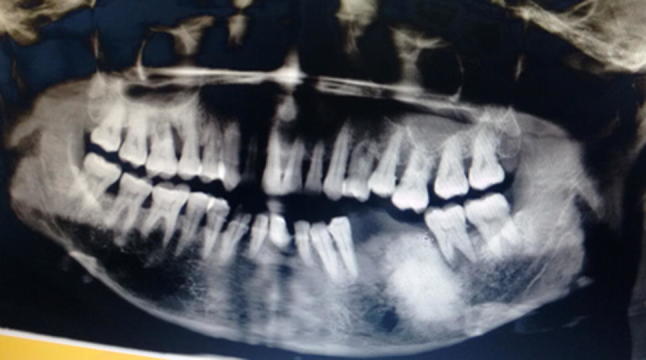

An orthopantomogram (OPG) showed radiopaque mass measuring about 3x3 cm in left body of mandible showing classical sun burst appearance (Fig. 2). 3D MDCT scan showed large bony mass lesion involving left body of the mandible measuring 41.8 mm × 25.4 mm with osteoid bone matrix and adjacent periosteal reaction (Fig. 3). Axial view CT scan confirmed the clinical finding of lingual cortical expansion (Fig. 4). Clinical and radiographic features were strongly suggestive of osteosarcoma of body of mandible. Routine haematological investigations were done. An open biopsy was performed with direct incision over the bone in the representative region; adequate size of bone tissue was removed using straight hand piece and copious saline irrigation. Continuous oozing was observed from the lesion obscuring the field. Incisional biopsy was also obtained from overlying soft tissues. Haemostasis was achieved by using local haemostatic measures. Samples were sent for histopathological examination which on H and E stained section showed osteoid material with atypical osteocytes, at focal areas chondroblastic tissues with atypical cells were evident while few sections showed cellular areas blending into malignant osteoid tissues confirming the diagnosis of OS of body of mandible (Fig. 5). The soft tissue biopsy was inconclusive. Patient was then referred to oncology department for further management. There she underwent hemi-mandibulectomy with disarticulation followed by free fibula microvascular reconstruction and followed by adjuvant chemotherapy. Final diagnosis of osteosarcoma of body of mandible with a skip metastastatic lesion in mandibular condyle was confirmed from histopathology reports.

Fig. 2.

OPG showing characteristic “Sunburst” appearance of OS

Radiological feature is of utmost importance as it acts as guide for the pathologist to correlate with clinic-pathological findings. Radiographic attributes include widening of periodontal ligament space along with the enfeeblement of lamina dura around a jaw tumour [6, 7]. However our patient had previous history of extraction of tooth in the same region, so the latter finding was truant. Radiographic appearance is based on the histological changes present in particular stage of osteosarcoma. It may display either bone formation (osteogenic), bone destruction (osteolytic) or a combination of both. Our patient’s OPG showed diffuse radiopacity in left body of mandible similar to that of classic “sun burst” appearance of osteosarcoma indicating malignant changes in the process of osteoid formation. Though OPG acts as a chaperon in the differential diagnosis, it has its own pitfalls such as image distortion and magnification. CT scan or MRI scan can be used as an advanced diagnostic tool to conclude on a more definitive diagnosis. The CT scan of our patient clearly delineated periosteal reaction with bony expansile lesion and osteoid bone matrix showing strong proclivity towards OS.